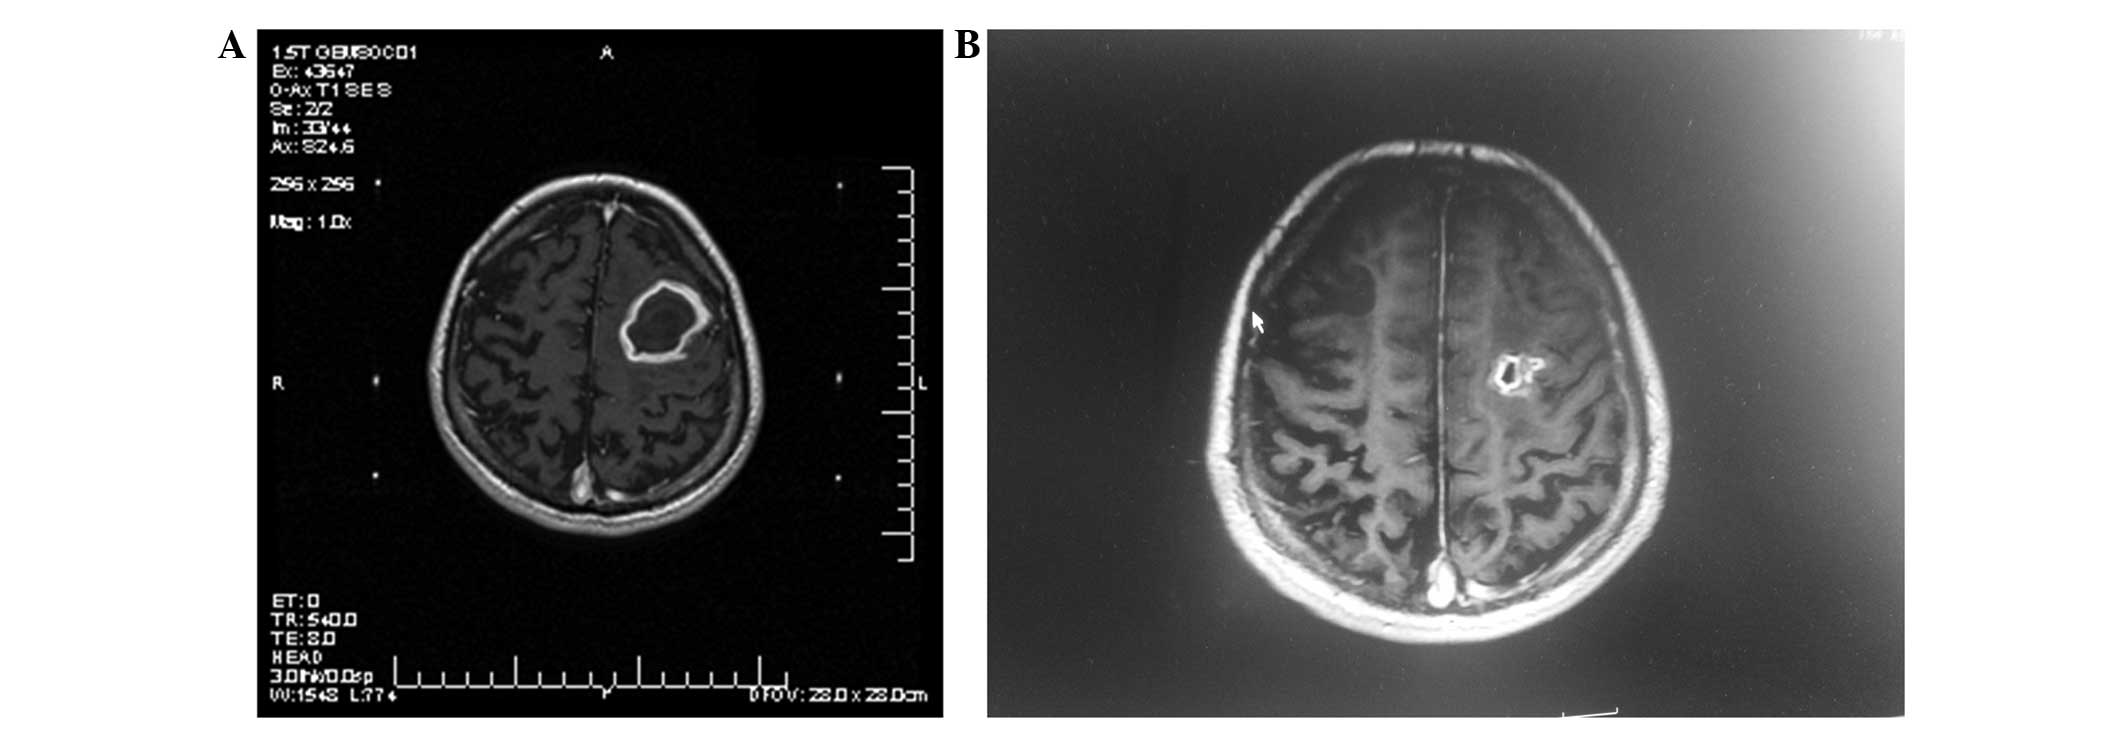

MRI was performed again after an interval of 3 months (Figs. 1 and 2). Tumor control was represented as a decrease in the tumor size following treatment. Progression of the local tumor was represented as an increase in size of the previously treated tumor. Moreover, the progression of the remote tumor was represented as the appearance of new brain metastases.

Figure 1.

T1-weighted (axial contrast-enhanced) magnetic resonance imaging of a 24-year-old woman diagnosed with a large cystic brain metastasis. The prescribed dose for the Gamma Knife radiosurgery (GKRS) was 16 Gy, with 0.5 mci colloidal phosphorus-32 radiation therapy. (A) Prior to aspiration. (B) Subsequent to aspiration at 3 months post-GKRS.